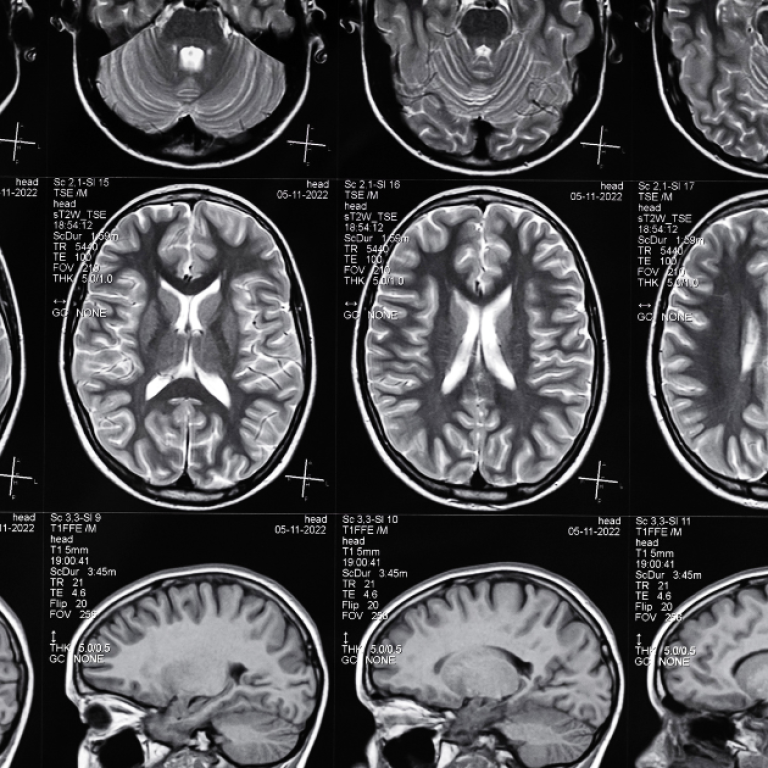

Kafa travmaları, ani bir darbe veya çarpma sonucunda ortaya çıkan ve beyin ile kafatasını etkileyebilen durumlardır. Hafif sarsıntılardan …

Beyin tümörleri, beynin kendi hücrelerinden kaynaklanan veya vücudun başka bir bölgesinden yayılan anormal hücre büyümeleridir. Bazıları yavaş ilerler, …